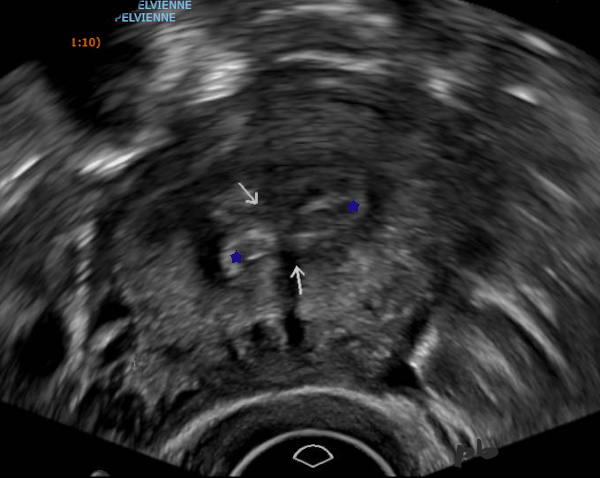

13 – Polypes multiples – Echographie vaginale

(même patiente que 12)

L’échographie complémentaire retrouve un endomètre hétérogène. Il existe un peu de liquide permettant de constater que l’endomètre est fin en réalité (►).

Ce liquide moule également une image hyperéchogène ovalaire (étoile blanche) : polype.

L’épaississement de la cavité est en rapport avec les nombreux polypes. Nombreux pédicules vasculaires en doppler.